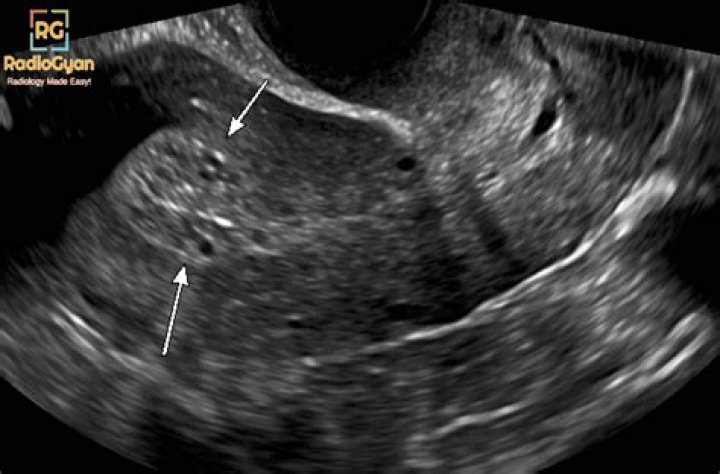

Is endometrium thick before period?

The part of your cycle between when you ovulate and when your period starts is called the secretory phase. During this time, your endometrium is at its thickest. The stripe accumulates fluid around it and, on an ultrasound, will appear to be of equal density and color throughout.

What is the normal size of endometrial thickness?

suggested upper limit of normal is <5 mm. the risk of carcinoma is ~7% if the endometrium is >5 mm and 0.07% if the endometrium is <5 mm. on hormonal replacement therapy: upper limit is 5 mm.

What percentage of endometrial biopsies are cancerous?

Conclusions: In a postmenopausal woman without vaginal bleeding, if the endometrium measures > 11 mm a biopsy should be considered as the risk of cancer is 6.7%, whereas if the endometrium measures < or = 11 mm a biopsy is not needed as the risk of cancer is extremely low.